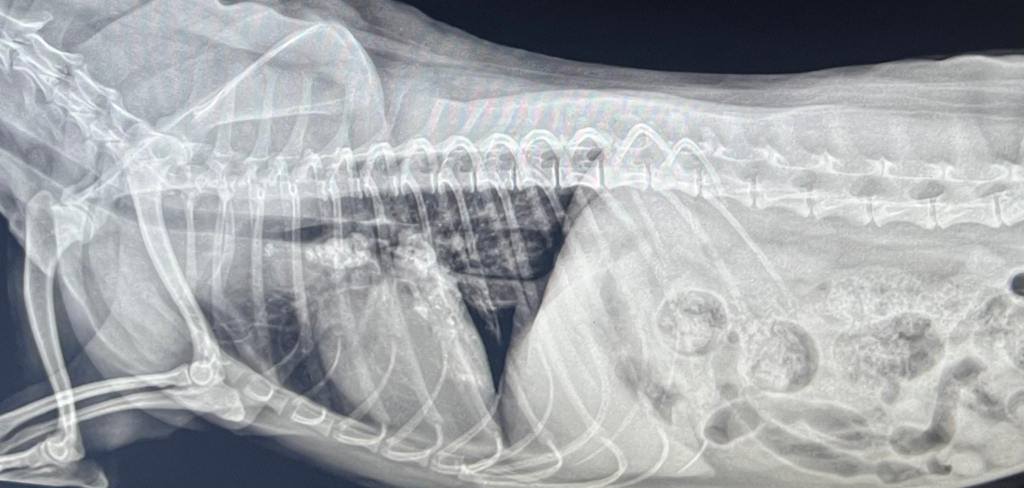

강아지 엑스레이 봐주세요…….

기침을 하는 증상 있습니다

폐종양 소견이 있는지 궁금합니다

기관지염 약을 주셨는데 도움이 되는지는 모르겠습니다

병원에서는 정확히 판단을 못내려주셨습니다..

폐렴의 여부는 엑스레이상 정확하게 판독은 안되지만, 등쪽으로 침윤이 되어 있는 경우는 폐렴, 폐수종, 폐출혈을 감별해야 합니다.

폐렴이라면 정확한 진단을 위해 PCR이 필요하며 1~2주 정도 내복약으로 항생제 복용하면서 follow up을 통해 균이 없어질 때 까지 항생제 치료를 합니다.

하지만 폐종양의 경우 흉부 방사선 보다는 CT촬영이 더 정확하니 큰 병원 가셔서 상담 받아보시기 바랍니다.

엑스레이 판독은 수직이 되는 두장 이상의 사진을 가지고 판단해야하며 원본 파일이 아닌 화면을 찍은 사진으로는 오진률이 높아져 원칙적으로 판독해서는 안됩니다.

또한 엑스레이에서 판독 가능한 종양의 크기는 5mm이상일때만 의미 있는데 해당 사진을 보고 직경을 평가할 수 없고

5mm이하의 종괴는 찾을 수 없으니 종양이 걱정되신다면 CT촬영을 하시기 바랍니다.